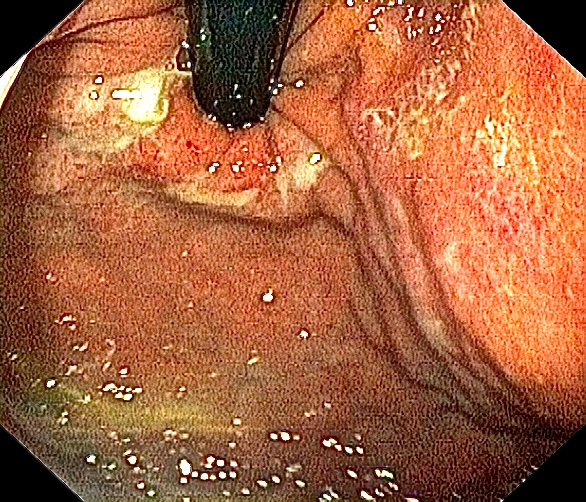

Omtrent samme bilde som ovenfor, tatt av meg tidligere. Bildet viser øsofagitt (betennelse i slimhinnene i spiserøret) forårsaket av hyppig oppkast, refluks av magesyre og overvekst av sopp og bakterier.